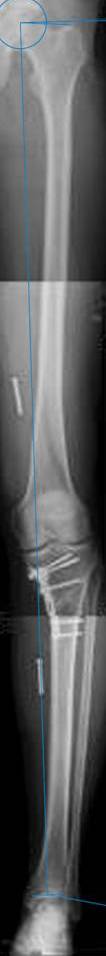

картинки оперированного пациента 40 лет, травма в 2006 году.

оперирован 06.11.2009г - корригирующая остеотомия большеберцовой кости.

Скажите, действительно ли эта остеотомия высокая?

Согласен с Вами, эта "скажем" не высокая остеотомия

Я картинку собрал с некоторыми погрешностями, если провести отвес от центра вращения головки бедра до середины голени (на пациенте),то имеется небольшой вальгус (гиперкоррекция)конечно она (гиперкоррекция) не достигает 10 гр, но 5 гр она достигает.

Уважаемый д-р Батал Шушания,

К сожалению, не очень удачный пример. Если верить Р-граммам, имеет место быть дисплазия мыщелков бедренной кости с наклоном суставной линии. Это уже создает сложности получения хороших отдаленных результатов. Кроме того, по классике, необходима гиперкоррекция с созданием вальгуса 7-10 градусов для максимальной разгрузки медиального отдела КС. Если верить укладке, то линия сустава имеет четкий варусный наклон, поэтому результат операции м.б. кратковременным. В этих случаях показана двойная остеотомия бедра и тибии.

Отправитель: Alexander Artemiev 10 Ноябрь 2009, 15:54

Здравствуйте, дорогие коллеги.

Впечатление искажает неправильная укладка.

Если сделать правильно, то видно, что бедренная кость в порядке, а цель остеотомии (низкой, кстати), не достигнута вовсе.

Сохраняется варус. Для того, чтобы создать вальгусную гиперкоррекцию, не моделируя при этом откровенный Х голени, можно сделать медиализирующую остеотомию.